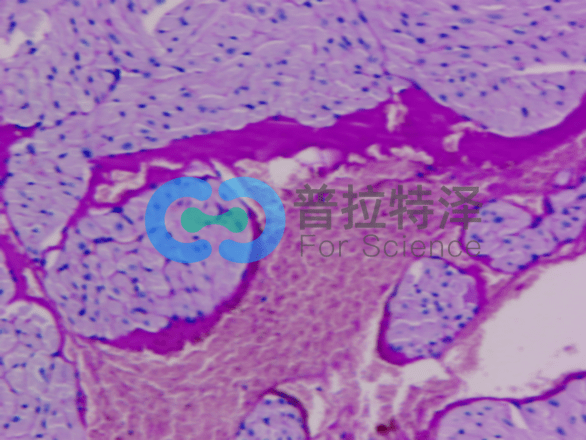

③消化道疾病診斷

在消化道疾病的診斷中,PAS染色對于觀察腸黏膜結(jié)構、黏液分泌及炎癥浸潤等具有重要意義。通過PAS染色,醫(yī)生可以判斷腸道疾病的類型及病變程度,為治療方案的制定提供依據(jù)。